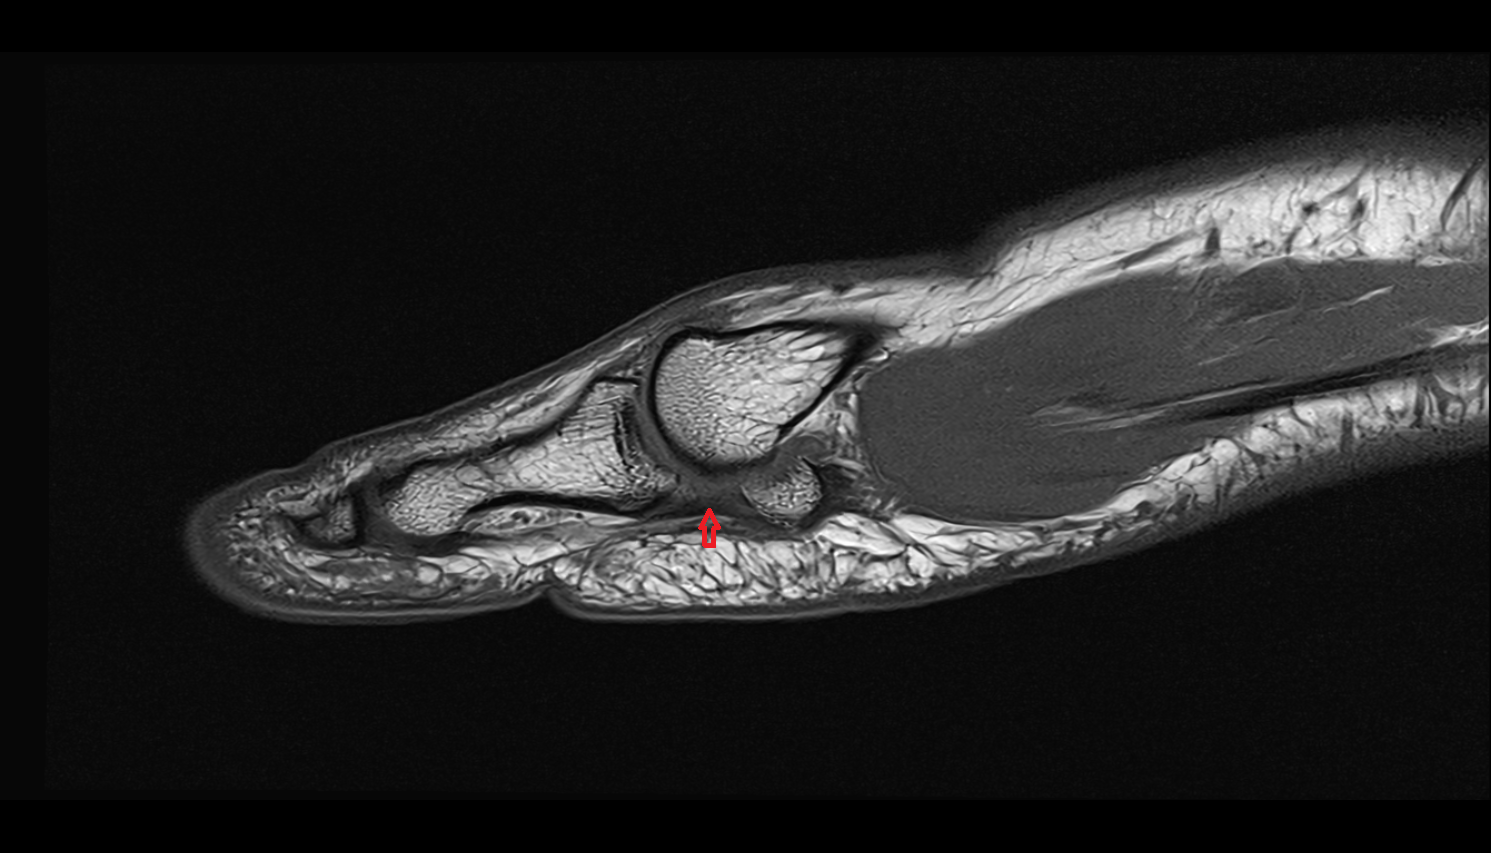

- Temporomandibular joint

- Mandibular condyle

- Mandibular fossa

- Articular eminence

- Articular surface of mandibular fossa

- Superior retrodiscal layer

- Superior synovial membrane of temporomandibular joint

- Articular disc of temporomandibular joint

- Intermediate zone of articular disc